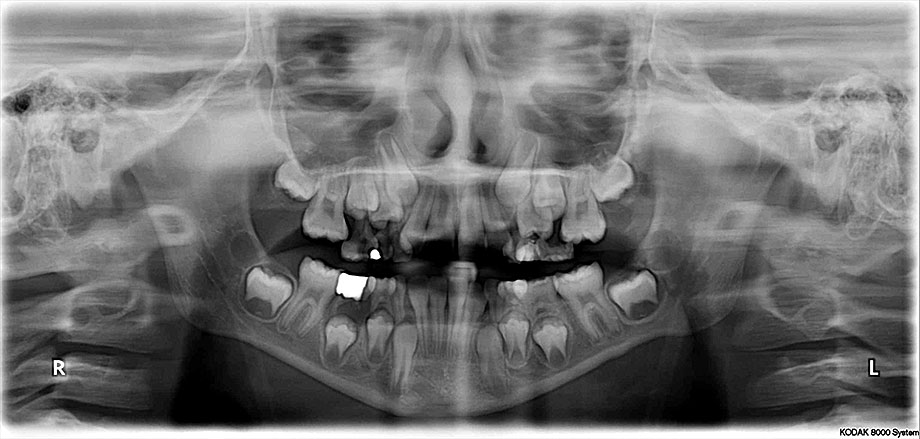

Dječja i preventivna dentalna medicina

RTG dijagnostika